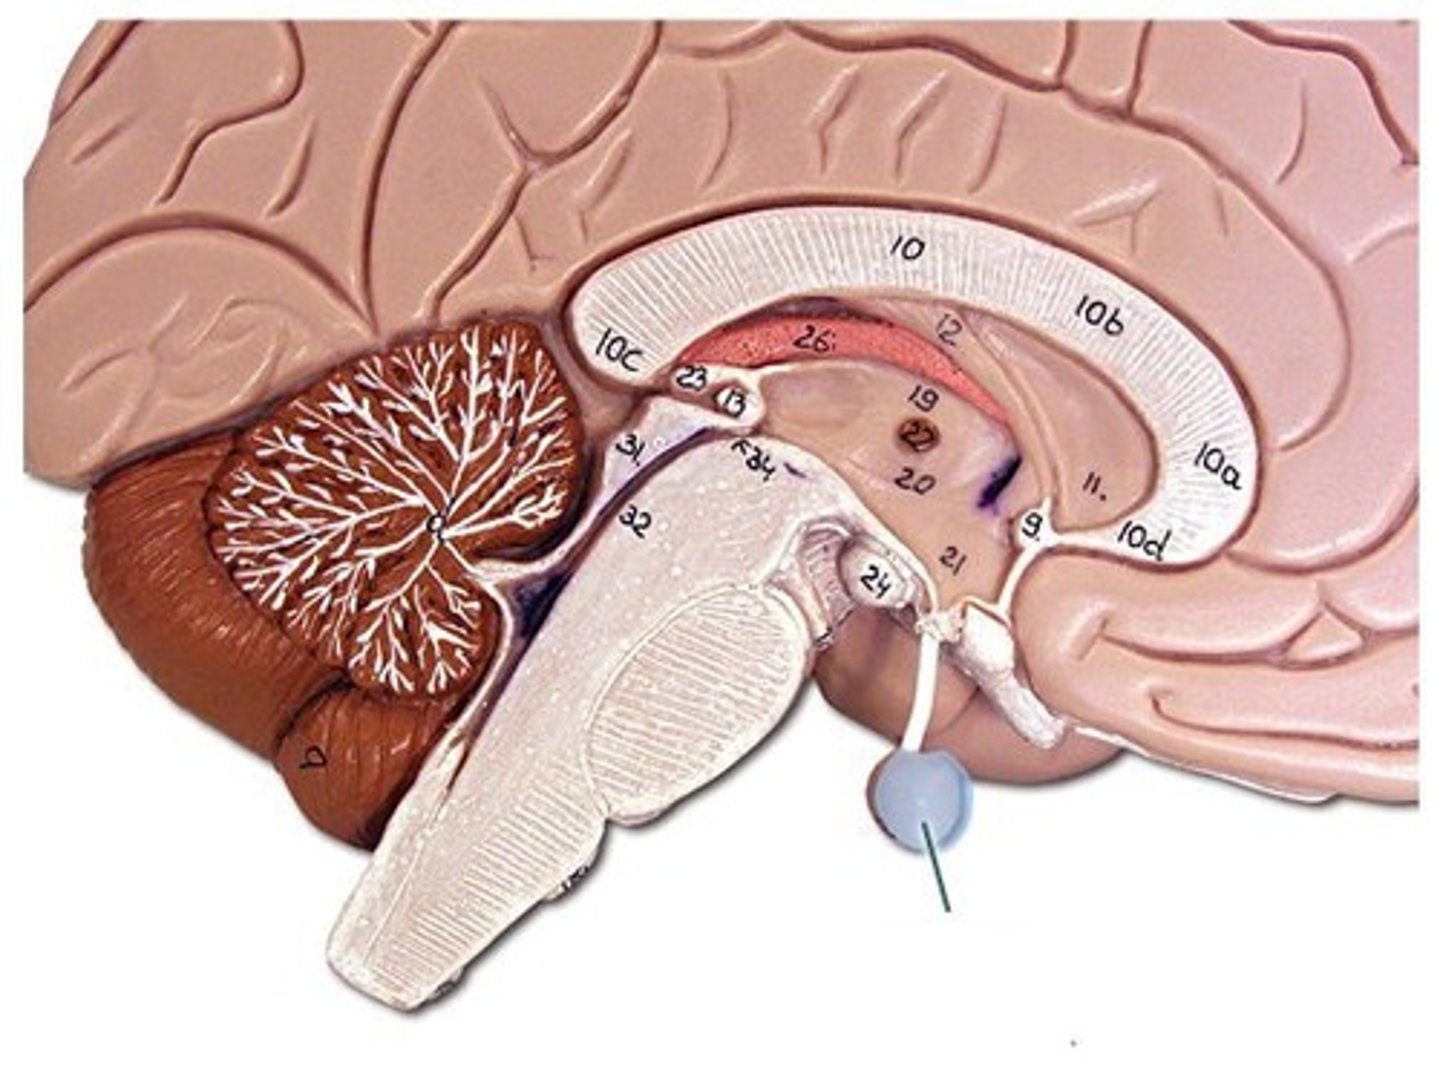

lateral ventricles

third ventricle

fourth ventricle

interventricular foramen

connects lateral ventricles to third ventricle

cerebral aqueduct

connects the third and fourth ventricles

choroid plexus

on the floor of all the ventricles, produces CSF

medulla oblongata

basic life support, heart beating, etc.

pons

control of breathing

midbrain

immediate reflexes

pituitary gland

produces hormones

mammillary bodies

olfactory relay stations

pineal gland

regulates sleep-wake cycles, secretes melatonin

cerebellum

balance, equilibrium, gross motor movement

arbor vitae

"tree of life," white matter of cerebellum